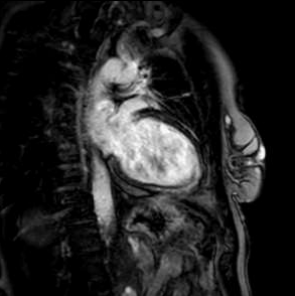

Cardiac magnetic resonance revealed left ventricle with characteristics of post-toxic cardiomyopathy and severely reduced global contractility with EF 34% (Image. 3- midmyocardial late gadolinium enhancement-LGE). Two chamber cine best visualized a cardiac mobile mass (11x7mm) attached to a small stalk to mid segment of the anterior wall of the left ventricle. The mass showed isointense signal on T1 (Image. 4), high intensity signal on T2 (Image. 5) and homogeneous late gadolinium enhancement (Image. 6). Characteristics were consistent with papillary fibroelastoma with differential diagnosis for myxoma or metastasis.

Image 4. CMR- isointense signal on T1